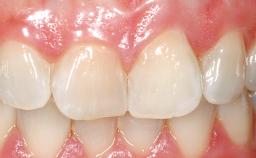

Late Placement of an Implant in a Maxillary Left Central Incisor Site

On examination, the patient had a low lip line and only displayed the coronal half of the anterior teeth when smiling.

Mesio-Distal Space Symmetry +/- 1 mm of contra-lateral tooth